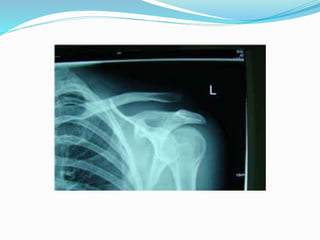

El documento trata sobre la anatomía y la funcionalidad del complejo articular del hombro, enfocándose en espacios quirúrgicos específicos en la región posterior. Se presenta información relevante sobre la cintura escapular y su relación con el hombro. El análisis realizado por el Dr. Luis Francisco Chávez Flor abarca aspectos clave para la comprensión de procedimientos quirúrgicos en esta área.